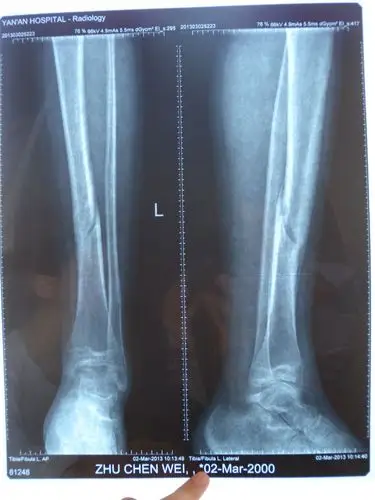

13岁男孩,骨折已4月 尚未愈合